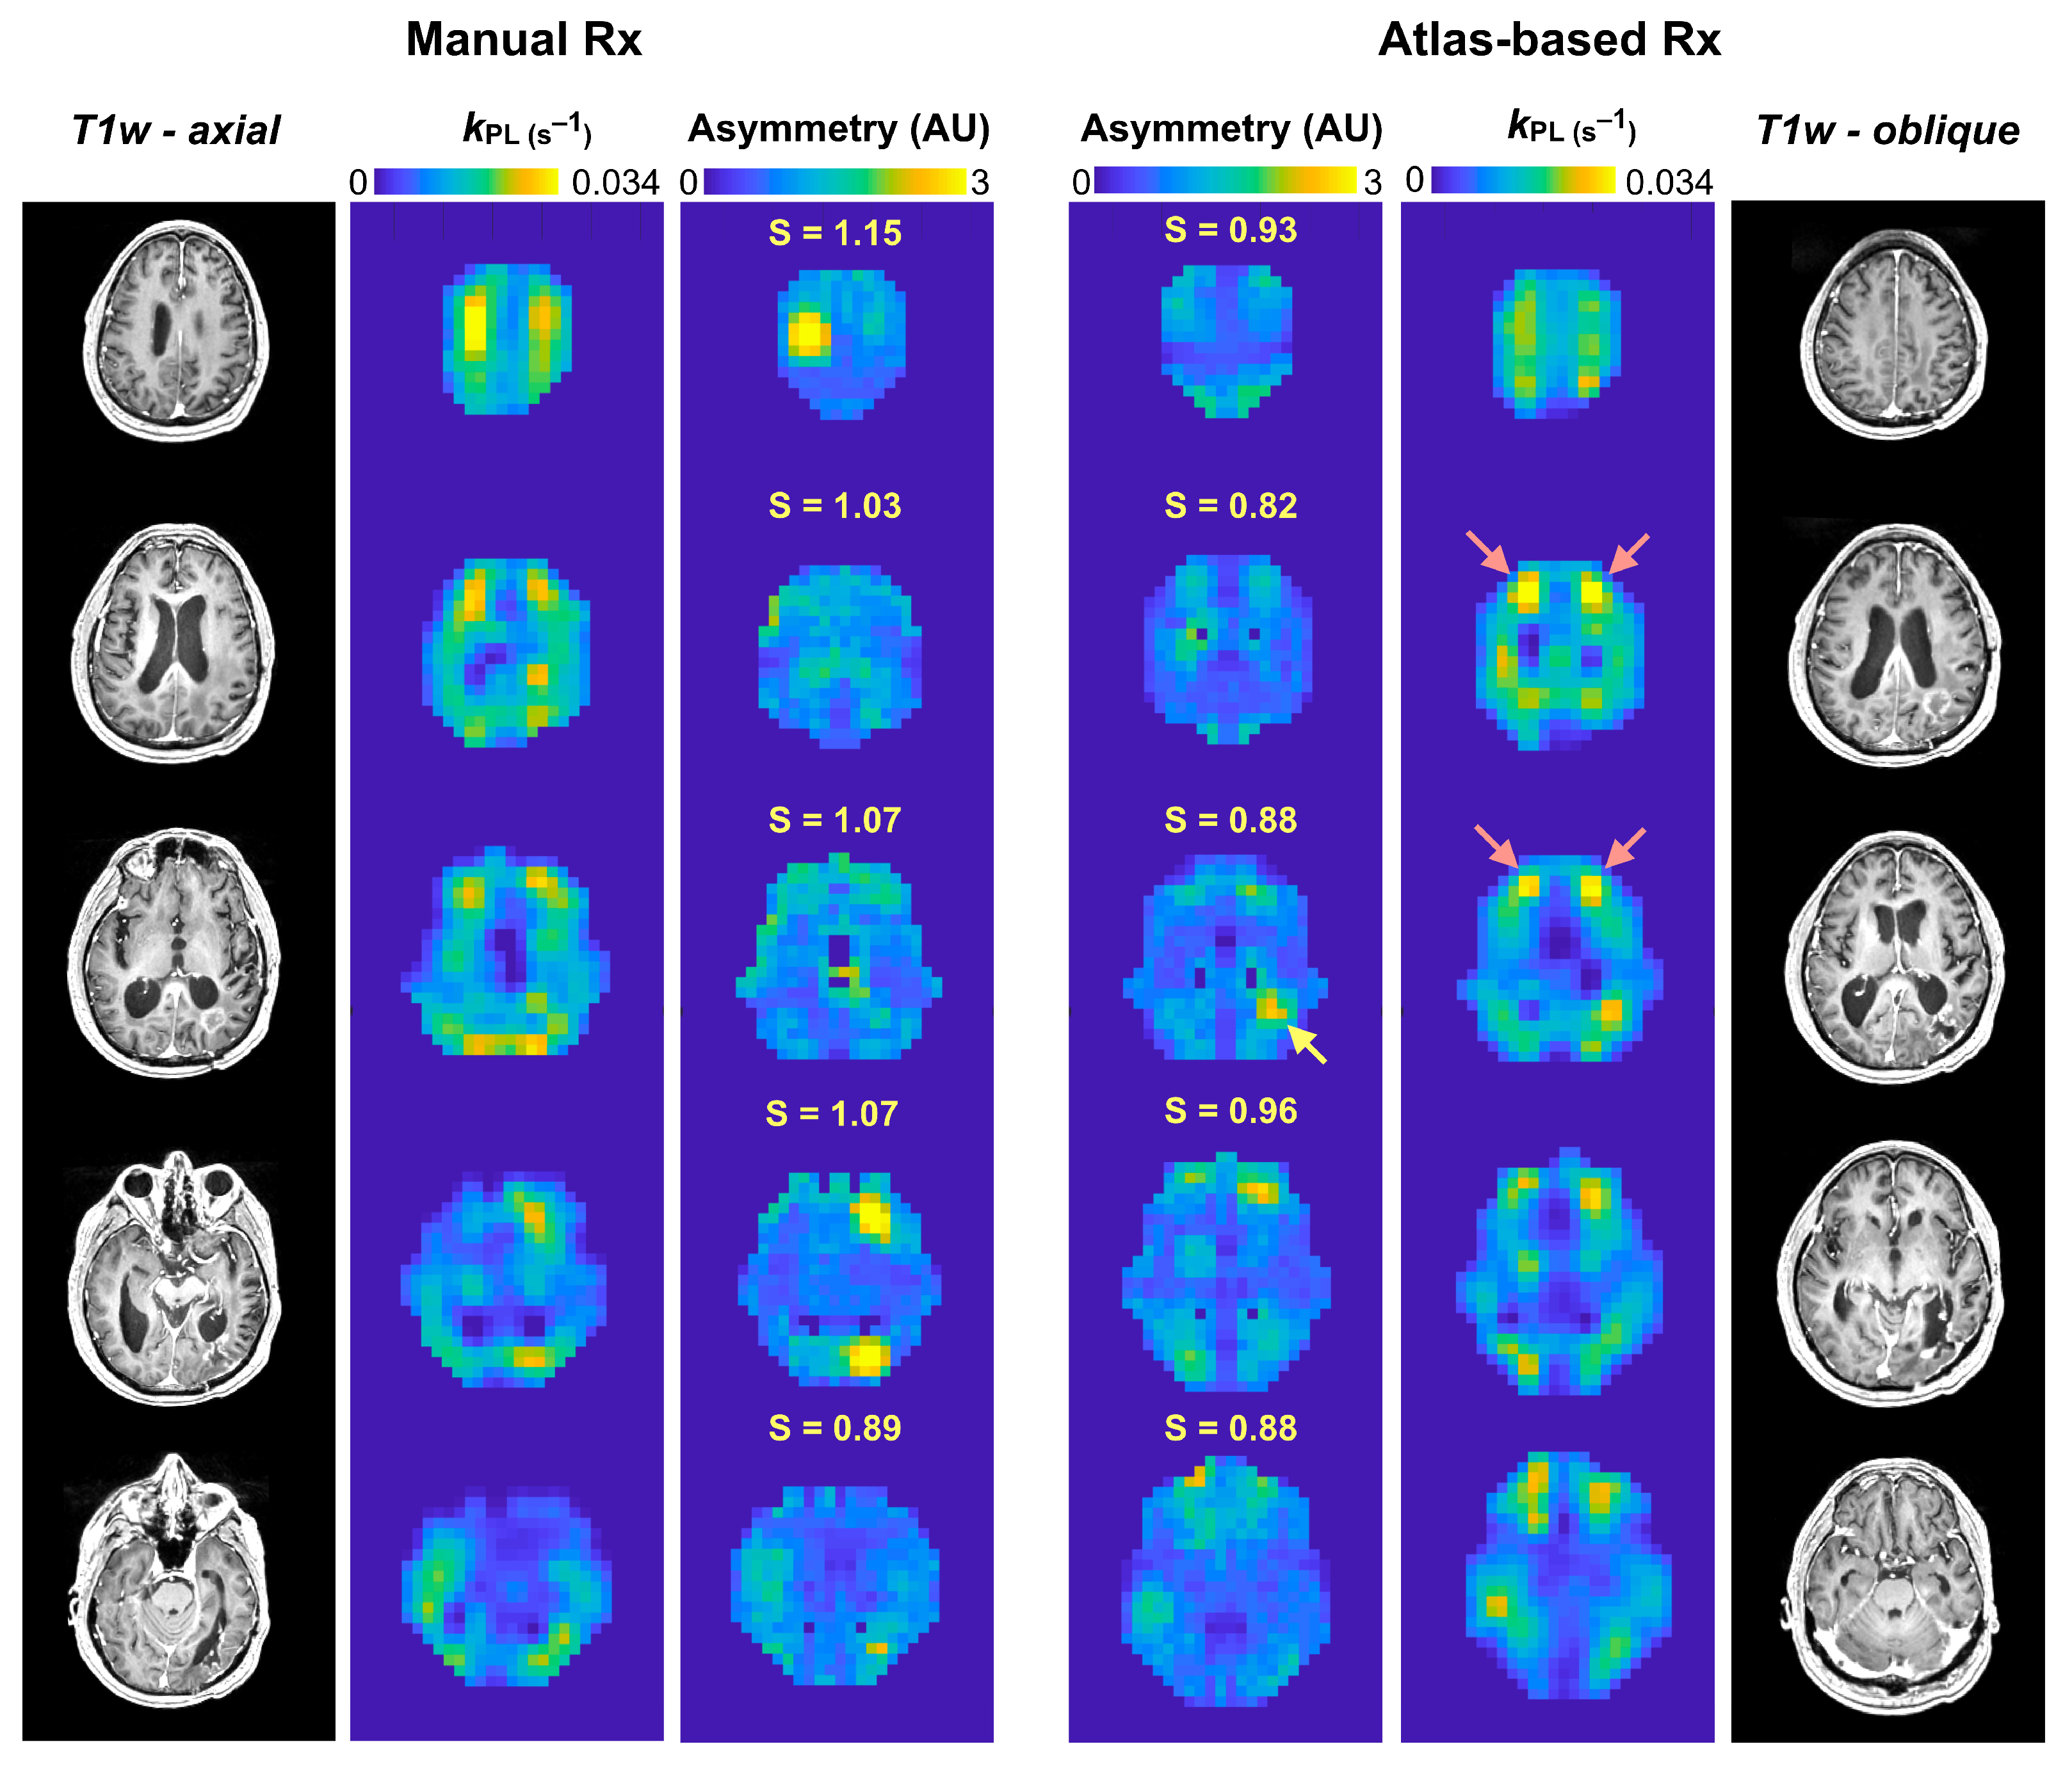

3.2. Serial Atlas-Based HP-13C EPI

3.3. Asymmetry in EPI Kinetics

| Hemispheric asymmetry, kPL (S) | 0.939 ± 0.039 | 0.970 ± 0.074 | <0.05 |